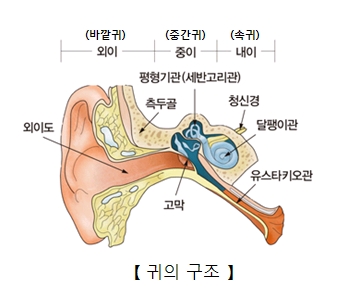

외상에 의한 고막 천공은 소리의 전달에 중요한 역할을 하는 고막이 외부의 충격에 의해 찢어지거나 구멍이 나서 손상되는 것을 말합니다.

귀의 통증은 오래가지 않지만 고막이 온전하지 않으므로 청력이 감소하고 귀울림이 있을 수 있습니다. 고막이 손상을 입으면서 고막 주변에 출혈이 발생하여 귀 밖으로 피가 흘러나오기도 합니다. 만약 귀 밖으로 고름이 나오면 손상된 고막 주위에 이차적인 세균 감염이 발생했을 가능성이 있습니다. 고막뿐만 아니라 귀안의 다른 구조물에도 손상이 생겼다면 청력이 크게 감소하거나 어지럼증이 발생할 수도 있습니다.

고막의 손상 여부는 이경이나 귀 내시경을 이용해 고막을 진찰하여 진단할 수 있습니다. 고막을 진찰하여 고막이 파열된 부분의 위치와 크기 등을 확인합니다. 고막 파열로 인한 청력 감소의 정도는 청력 검사를 통해 확인할 수 있습니다. 고막뿐만 아니라 귀안의 다른 구조물의 손상이 의심되는 상황이라면, 측두골 단순 방사선 검사나 CT 검사를 받을 수도 있습니다.